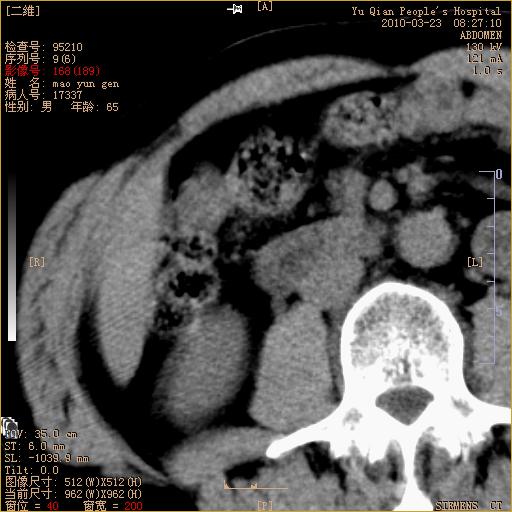

标题: CT25266:消瘦月余,前来肝部检查,请看看肠腔 [打印本页]

标题: CT25266:消瘦月余,前来肝部检查,请看看肠腔

肝区结肠占位,腺癌可考虑,建议肠镜活检。

升结肠肠壁增厚,不均强化,考虑升结肠腺癌可能性,建议肠镜检查。

1)考虑升结肠癌。2)右肾小囊肿。